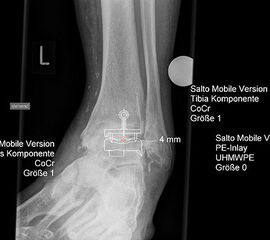

Planung einer Prothesenversorgung am oberen Sprunggelenk.

Abbildung 6